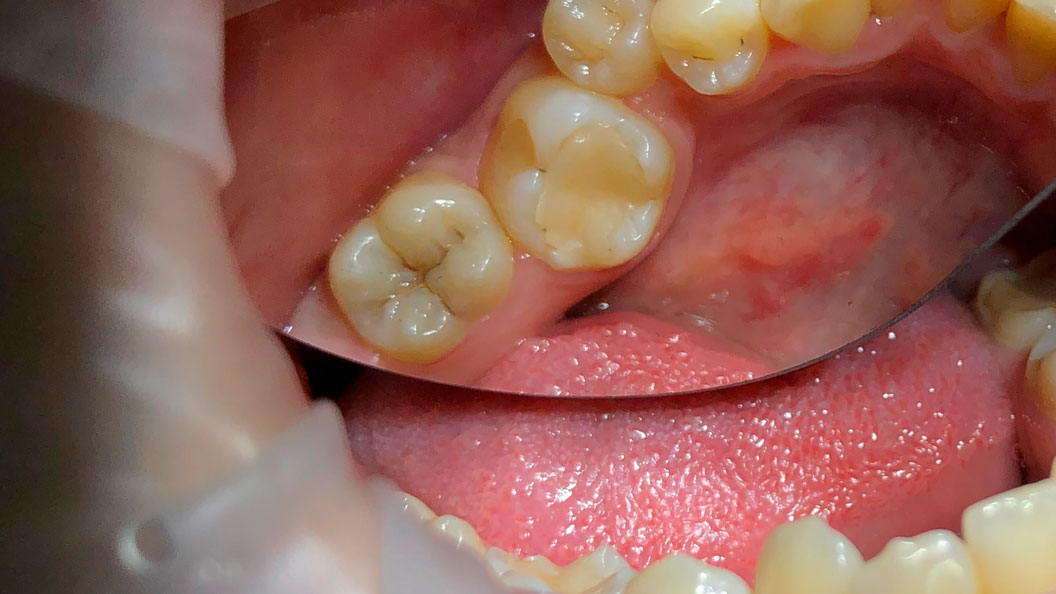

В «Стоматологию Комфорта» обратился пациент с жалобами на боль в нижнем зубе с правой стороны при употреблении в пищу сладкого. В результате проведённого осмотра врачом Магомедовым был поставлен диагноз: кариес дентина 4.7 зуба. Проведено лечение с применением коффердама и установкой пломбы Estelite А3.

Пломбы Estelite – это инновационный материал с высокими эстетическими показателями, который предназначен для зубов, поражённых кариесом. Estelite выглядит естественно, имеет высокий уровень прочности и быстро полимеризуется под воздействием светового излучения. Состоит из кремниево-циркониевого и композитного наполнителей.

В ходе лечения врач провёл следующие манипуляции:

- инфильтрационная анестезия;

- механическая обработка полости под контролем кариес-маркера;

- медикаментозная обработка;

- постановка пломбы из композита Estelite.